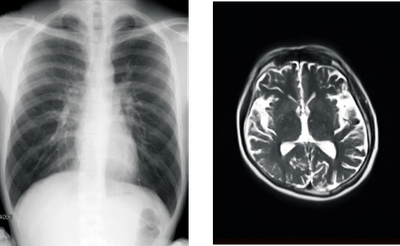

賛育会病院では2021年10月11日より、「カルテコ」で健診情報が閲覧可能になりました。今回新たに、健診・人間ドックで撮影したレントゲン・マンモグラフィ・CT(コンピュータ断層撮影)・MRI(磁気共鳴画像診断)などの検査画像が閲覧できるようになります。21年1月以降の過去のデータまでさかのぼって閲覧することができます。